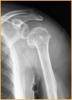

锁定板治疗老年人骨质疏松性移位的肱骨近端骨折

患者女,72岁,诊断为:肱骨近端骨折。

行肱骨近端锁定型钉板(PHILOS)固定术,手术过程:采用全麻或斜方肌阻滞麻醉,用沙滩椅体位,术中肱骨头复位后,用二至三枚克氏针临时固定保持复位,并使其余骨折块复位,然后透视确认复位质量。用5号不可吸收缝线将大小结节缝合修复,再选用适当长度的锁定钉板置于肱骨近端和肱骨干的外侧面。注意避免将钢板放置的过高以致成角螺钉的位置不合适而不能达到最佳骨接触。可用一枚非锁定螺钉固定于肱骨干上可使钢板远近端滑动调整位置。然后使用导向器上锁定螺钉使钢板和螺钉一体化。固定完成后再次透视确认无误,处理好软组织后逐层关闭切口。